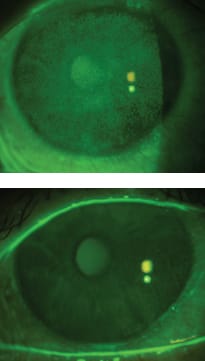

Entering visual acuity with spectacles was 20/25 OD and 20/40 OS. Figure 3 shows the appearance of his corneal staining. The corneal staining of each eye appears fairly similar despite his left eye being more symptomatic. As in the last example, there were no significant anatomical obstacles that challenged the design. The goals for fitting this patient were to improve the ocular comfort and also to improve visual acuity. The patient observed immediate relief upon application of both diagnostic devices.

Figure 3. Pre-fitting photos of corneal staining OD and OS for Patient #2 who suffers from cGVHD.

The final scleral lenses were 20.0mm in diameter. He achieved 20/20 OD and 20/25 OS visual acuity. The patient reported optimal comfort all waking hours (Figure 4); ultimately, his goals were met.

Figure 4. Patient #2 (cGVHD) after 5 hours lens wear.

This patient began wearing 18.0mm devices in the beginning of the fitting process. As mentioned before, some patients are aware of the tissue that is not covered by the lens. He was successfully trained with application and removal of the 18.0mm spherical devices (540µm sagittal depth), but he complained of symptoms of wind and exposure outside of the area of the lens. His complaint warranted a trial with a larger, 20mm diameter device. He observed an improvement with this trial. The change in the diameter was essentially like starting over, but ultimately it was beneficial. His final correction OD was an against-the-rule (ATR), back-surface toric, 20.0mm overall diameter lens, 620µm sagittal depth from the flat meridian and 250µm difference between the flat and steep edge. The left lens was a 20.5mm overall diameter, ATR, back-surface toric design with 645µm of sagittal depth from the flat meridian and 250µm of toricity.

Along with ocular surface abnormalities, debris is the most common problem encountered with dry eye patients. If a spherical design was used in either eye, not only would Patient #2 suffer from front-surface debris, but it would be compounded with reservoir debris as well. The back-surface toricity improves alignment of the lens to the sclera and reduces the excessive tear exchange that carries the debris (Figure 5).

Figure 5. The first image shows diffuse front-surface debris in a patient who has keratoconjunctivitis sicca. The second image shows an example of debris in the reservoir of the device. Finding the path or pattern of debris provides an opportunity to improve the alignment of the device to the sclera.